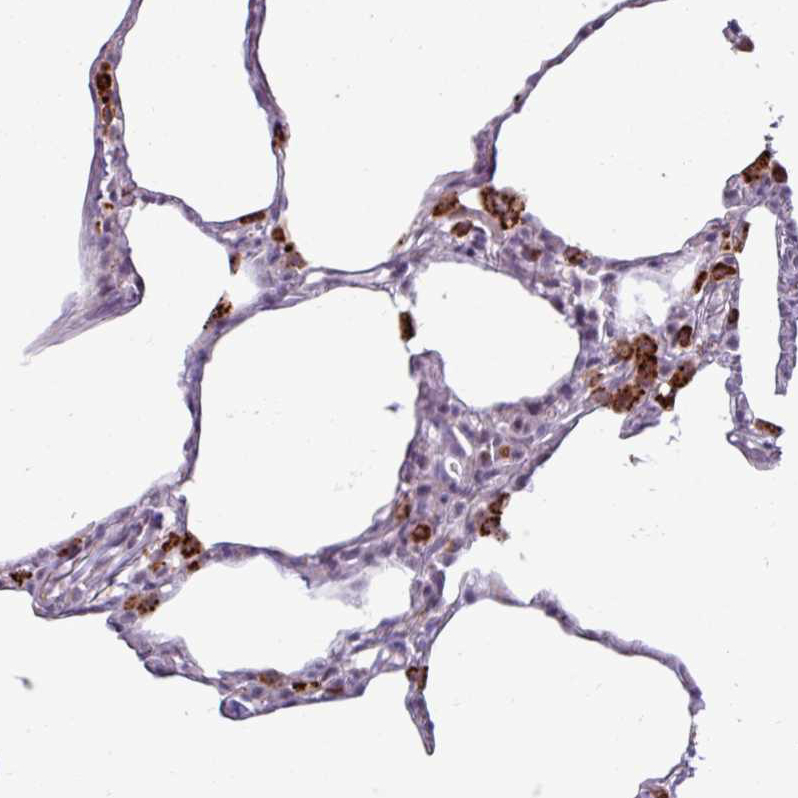

Immunohistochemical staining of human lung shows strong granular cytoplasmic positivity in macrophages.